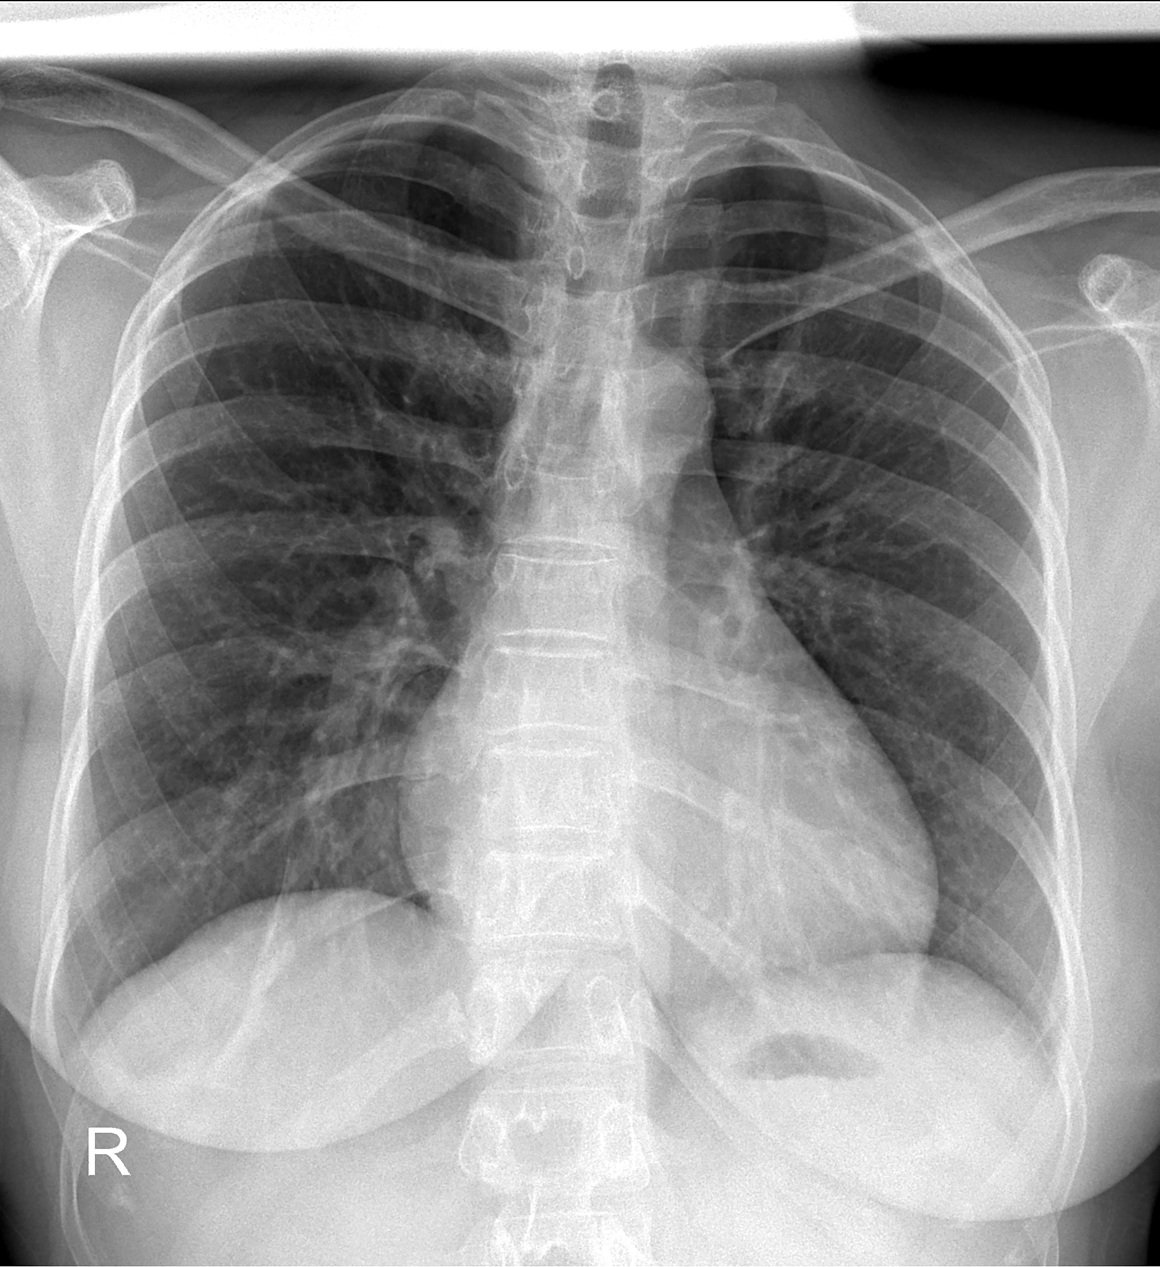

Plućni parenhim – najčešći radiološki nalazi

Najčešći radiološki nalazi plućnog parenhima:

• plućni parenhim dostupan analizi ovaj opis znači da je plućno tkivo jasno prikazano na snimci te da se može detaljno procijeniti; obično ne upućuje na patološki nalaz, već na tehničku kvalitetu snimke

• ožiljne promjene plućnog parenhima – posljedica ranijih oštećenja pluća (nakon infekcija ili upala); najčešći uzroci su tuberkuloza, upala pluća, prethodne kirurške intervencije, radioterapija, trauma

• smanjena prozračnost plućnog parenhima – zrak u plućima je djelomično zamijenjen tekućinom, stanicama ili gustom tvari; najčešći uzroci su upala pluća, plućni edem, hemoragija, atelektaza

• plućni parenhim – konsolidacija označava zbijenost plućnog tkiva zbog ispunjenja alveola eksudatom, gnojem, krvlju ili stanicama; najčešći uzroci su bakterijska pneumonija, plućna hemoragija, aspiracija, maligni infiltrat

• pojačana prozračnost plućnog parenhima – plućno tkivo sadrži više zraka nego što je uobičajeno; najčešći uzroci su emfizem, astma, opstrukcija bronha (tumor, strano tijelo), pneumotoraks.